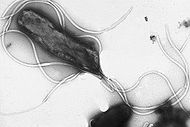

Helicobacter pylori ( / ˌ h ɛ l ɪ k ɵ ˈ b æ k t ər p aɪ ˈ l ɔər aɪ /; H. pylori), previously named Campylobacter pyloridis, is a Gram-negative, microaerophilic bacterium found in the stomach. It was identified in 1982 by Barry Marshall and Robin Warren, who found that it was present in patients with chronic gastritis and gastric ulcers, conditions that were not previously believed to have a microbial cause. It is also linked to the development of duodenal ulcers and stomach cancer. However, over 80 percent of individuals infected with the bacterium are asymptomatic and it has been postulated that it may play an important role in the natural stomach ecology.

More than 50% of the world's population harbour H. pylori in their upper gastrointestinal tract. Infection is more prevalent in developing countries, and incidence is decreasing in Western countries. H. pylori's helix shape (from which the generic name is derived) is thought to have evolved to penetrate the mucoid lining of the stomach.

H. pylori is a helix-shaped (classified as a curved rod, not spirochaete) Gram-negative bacterium about 3 micrometres long with a diameter of about 0.5 micrometres. It is microaerophilic; that is, it requires oxygen, but at lower concentration than is found in the atmosphere. It contains a hydrogenase which can be used to obtain energy by oxidizing molecular hydrogen (H2) produced by intestinal bacteria. It produces oxidase, catalase, and urease. It is capable of forming biofilms and can convert from spiral to a possibly viable but nonculturable coccoid form, both likely to favour its survival and be factors in the epidemiology of the bacterium.